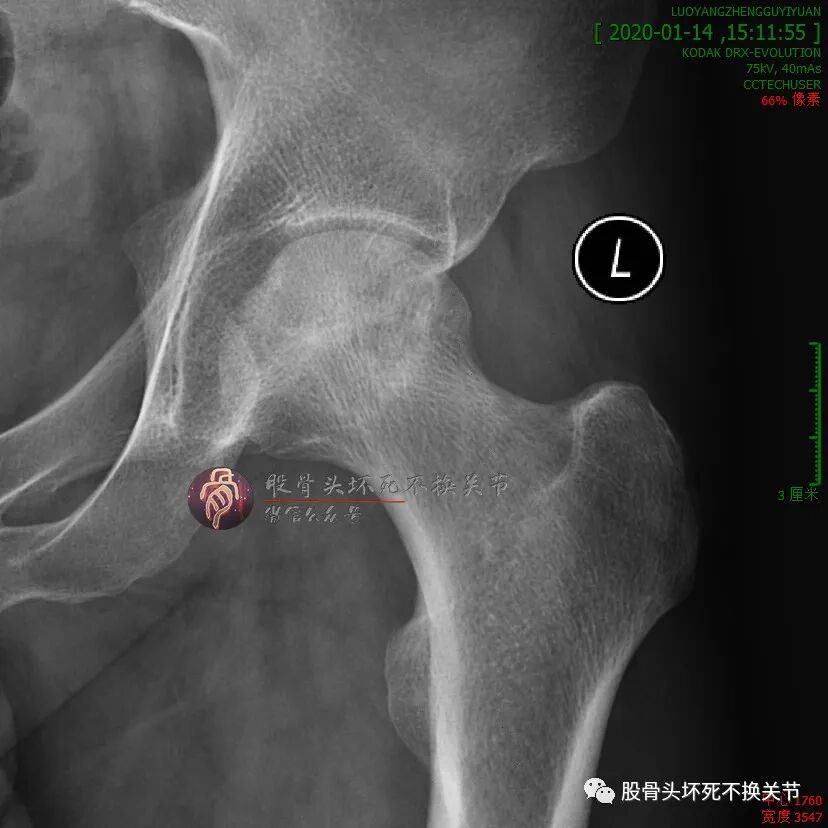

初次就诊2年后:

不错嘛,在工作、生活没耽误的前提下,病人偶尔来医院复查或治疗,也没有想象中的那么不便。初次就诊近3年复查:

这股骨头杠杠的!